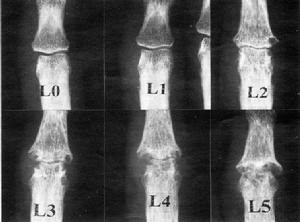

![FELTY綜合症[費爾蒂綜合徵] FELTY綜合症[費爾蒂綜合徵]](/img/7/33a/nBnauM3X2UTM1YjN4EDM5QjNyITMyYjN0YjMwADMwAzMxAzLxAzLzAzLt92YucmbvRWdo5Cd0FmLxE2LvoDc0RHa.jpg)